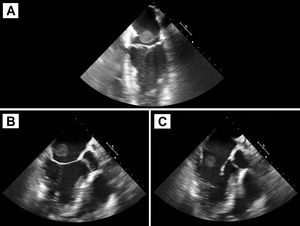

Tres años después, el paciente acudió a urgencias por fiebre de 2 semanas de evolución y antecedente reciente de avulsión ungueal traumática del primer dedo del pie, sin mejoría a pesar de tratamiento antibiótico empírico con amoxicilina/ácido clavulánico, que posteriormente pasó a cefuroxima. Asociaba leucocitosis y aumento de reactantes de fase aguda. Los hemocultivos extraídos al ingreso y a las 48h fueron positivos para Staphylococcus aureus meticilín-sensible, por lo que se inició tratamiento con cloxacilina y daptomicina. Ante sospecha de EI se solicitó ecocardiografía transtorácica, sin hallazgos patológicos. No obstante, en la ecocardiografía transesofágica, se objetivó una masa móvil de gran tamaño anclada a la vertiente auricular izquierda del dispositivo de cierre de FOP, con protrusión hacia la válvula mitral, compatible en ese contexto con vegetación endocardítica (fig. 1).

Debido al gran tamaño de la masa, se decidió cirugía emergente. Bajo circulación extracorpórea y con pinzado aórtico, se realizó la atriotomía derecha para acceder al dispositivo. Se procedió a su resección, objetivando en la vertiente auricular izquierda un absceso adherido al dispositivo (fig. 2). Posteriormente, se reconstruyó el septo interauricular con parche de pericardio heterólogo. La evolución postoperatoria del paciente fue satisfactoria, con una estancia en unidad de cuidados intensivos de 3 días y siendo dado de alta hospitalaria al octavo día postoperatorio. Se desescaló la antibioterapia a cloxacina aislada durante 4 semanas adicionales.